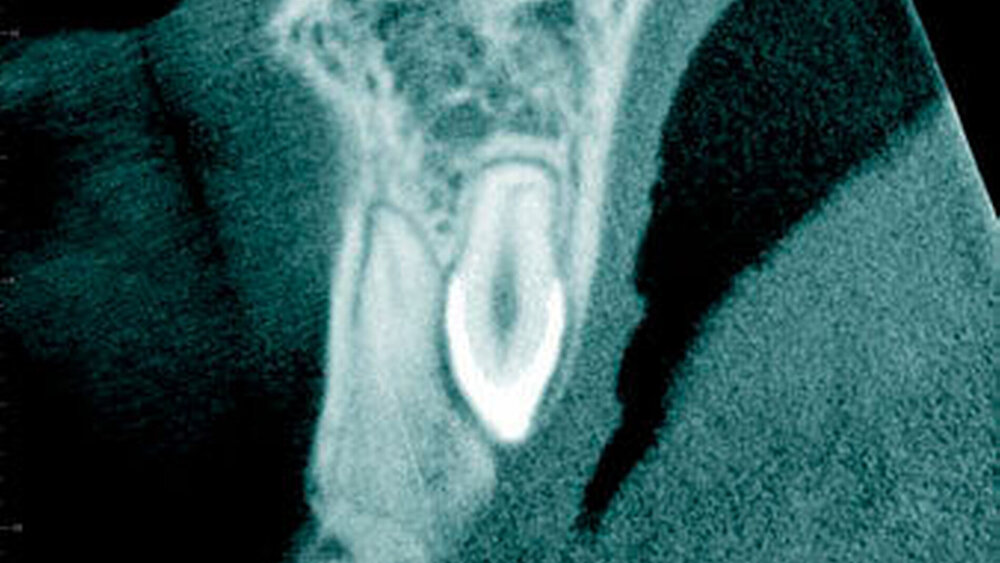

In einer aktuellen Arbeit berichteten Mossaz und Mitarbeiter (2014) über eine relativ hohe Prävalenz (22,8 Prozent) der Wurzel- resorptionen an benachbarten Zähnen, wobei besonders häufig überzählige Prämolaren zu Resorptionen führen (Abbildung 18). Für die Beurteilung der Wurzelresorptionen wurden digitale Volumentomografie (DVT) der Patienten herangezogen. In einer Studie aus China, welche ebenfalls DVT-Bilder beurteilte, wurde über eine deutlich geringere Häufigkeit von Wurzelresorptionen (1,6 Prozent) berichtet [Liu et al., 2007]. Im Gegensatz zu den Daten aus der Schweiz war Diagnose und Bewertung von Wurzelresorptionen kein primäres Ziel dieser Studie und es wurde auch keine Information über das Ausmaß der Resorptionen gegeben.

Daher könnte diese Studie leichte oder mäßige Wurzelresorptionen nicht eingeschlossen haben, was zumindest einen Teil des doch deutlichen Unterschieds in den Prozentsätzen erklären würde. Studien, welche Panoramaschichtaufnahmen zur Diagnose von Wurzelresorptionen heranziehen, berichten über Resorptionsraten zwischen 4,7 Prozent [Gündüz et al., 2008] und 7,6 Prozent [Hyun et al., 2009]. Tyrologou und Mitarbeiter (2005) berichteten sogar, dass keine Resorption im untersuchten Patientengut vorhanden waren. Allerdings wurden in dieser Studien nur Mesiodentes beurteilt, wo Wurzelresorption benachbarter Zähne eher selten vorkommen [Mossaz et al., 2014]. Generell lässt sich festhalten, dass zweidimensionale Röntgenaufnahmen für die Diagnose von Wurzelresorptionen eher ungenau sind und diese so in bis zu 50 Prozent der Fälle übersehen werden [Ericson Kurol, 1987, Heimisdottir et al., 2005; Botticelli et al., 2011; Alqerban et al., 2011a].

Überzählige Zähne können lange Zeit asymptomatisch bleiben und werden daher nicht selten erst zufällig diagnostiziert. Es werden aber auch eine Vielzahl an möglichen klinischen Komplikationen wie Zahndurchbruchstörungen, Lageverschiebungen/Rotationen sowie Wurzelresorptionen an benachbarten Zähnen und auch Zystenbildung in der Literatur beschrieben. Eine Wurzelresorption an Nachbarzähnen wird in bis zu 22,8 Prozent der Fälle im entsprechenden Röntgenbild beobachtet, wobei besonders häufig überzählige Prämolaren zu Resorptionen führen.

• Überzählige Zähne können zu diversen klinischen Komplikationen wie Zahndurchbruchstörungen, Lageverschiebungen/Rotationen sowie Wurzelresorptionen an benachbarten bleibenden Zähnen und auch zu einer Zystenbildung führen. Wurzel- resorptionen an Nachbarzähnen werden in bis zu 22,8 Prozent der Fälle im entsprechenden Röntgenbild diagnostiziert, wobei dies besonders häufig bei überzählige Prämolaren beobachtet wurde.